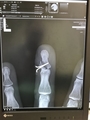

えーっと、mixiには書いていなかったのですが、2週間ほど前、仕事の集配途中に事故を起こしてしまい、右肩脱臼+左手指2本を骨折してしまいました。過去何度かバイクで事故を起こしたり巻き込まれたりってのはあったのですが、ここまでの重傷は初めて。体を起